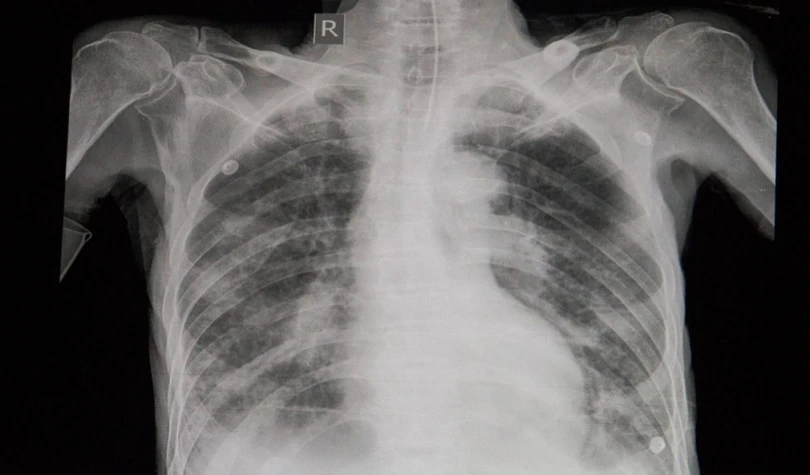

Nhiễm khuẩn thứ phát: Virus cúm có thể nguy hiểm chết người khi nó kích thích một bệnh khác, ví dụ như viêm phổi, viêm cơ tim, viêm não hay nhiễm trùng hệ thống. Đây là những phản ứng của cơ thể đối với nhiễm khuẩn thứ phát, dẫn đến viêm các nội tạng và có thể gây tử vong.

Khó thở: Khó thở hoặc thở gấp mà không phải do nghẹt mũi là những dấu hiệu cho thấy bạn đã gặp phải biến chứng của bệnh cúm. Các dạng nhiễm khuẩn thứ phát như viêm phổi có thể khiến bạn gặp phải tình trạng này.

Đau ngực hoặc đau bụng: Cảm giác đau tức ngực khi bị cúm có thể là dấu hiệu của viêm cơ tim hoặc viêm màng tim - các biến chứng của bệnh cúm.